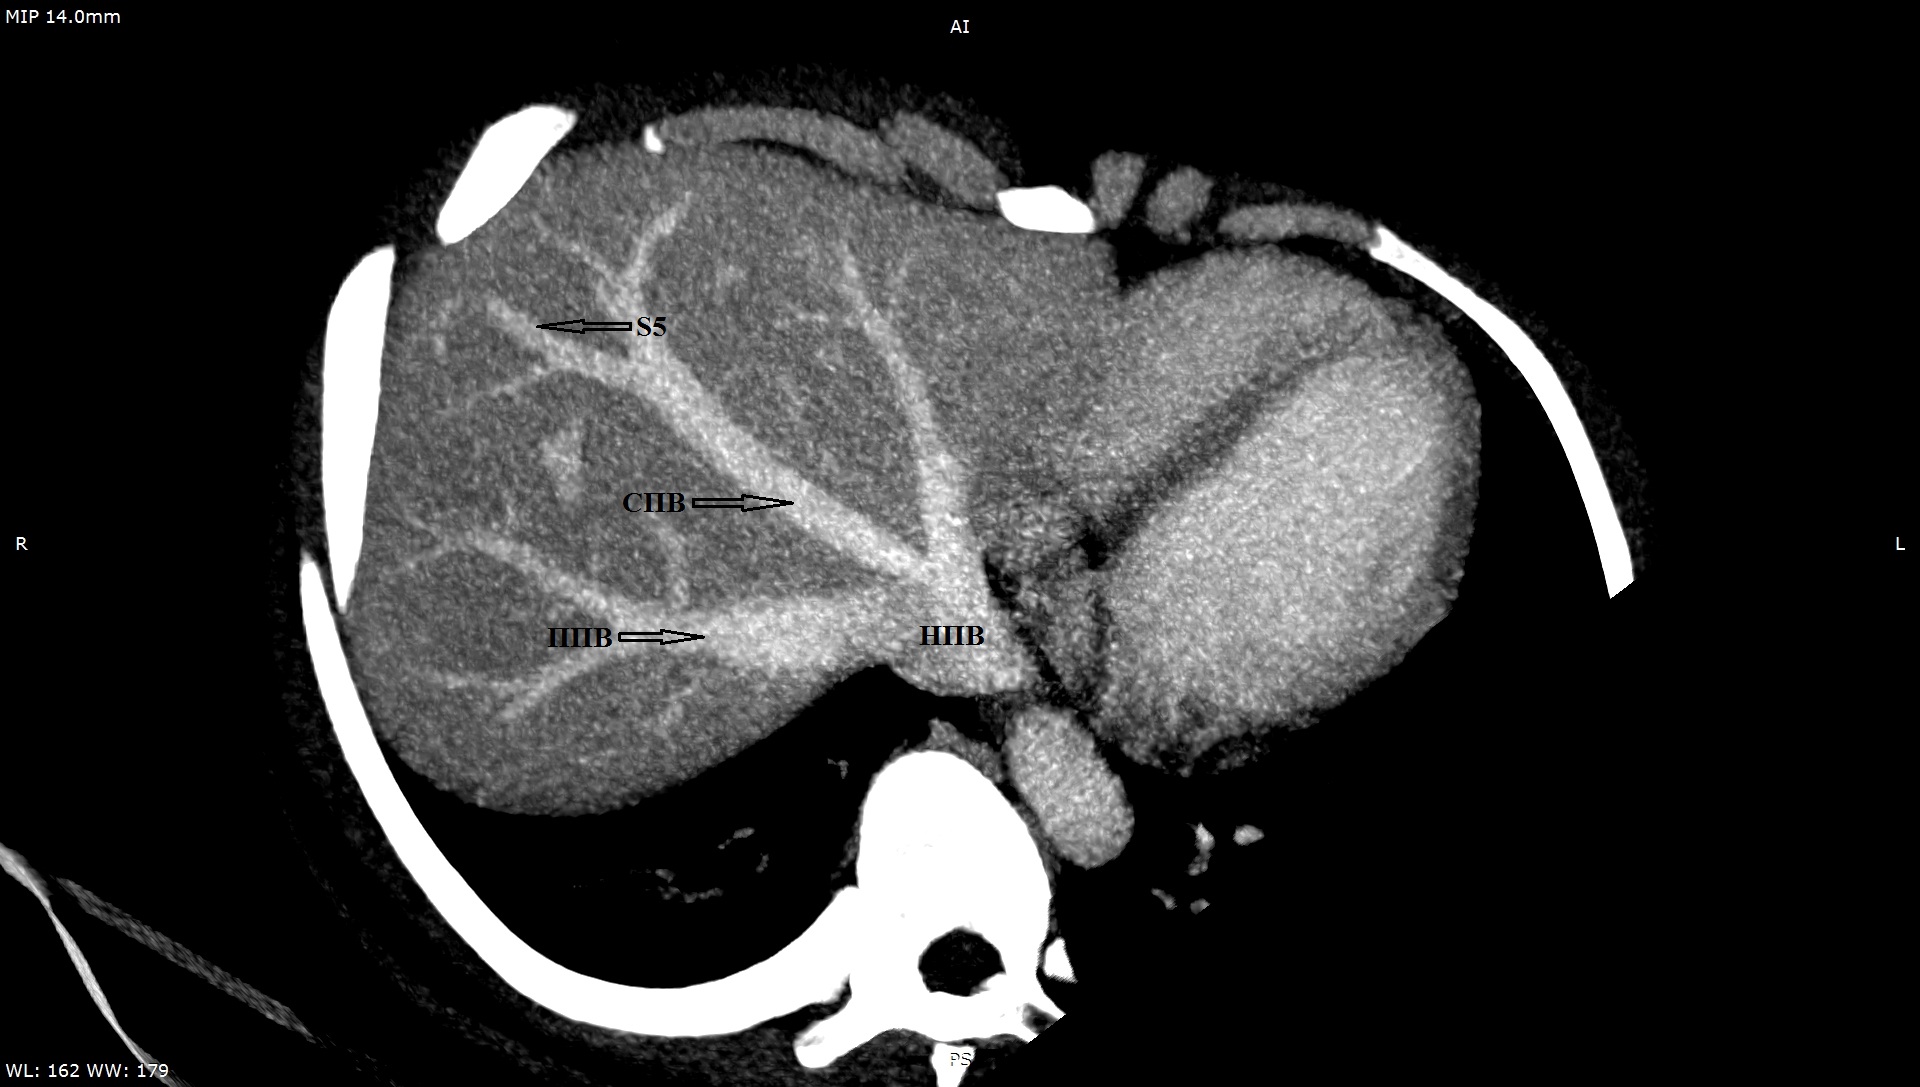

3. Тип А (снимок КТ). | |

6. Тип B (снимок КТ). | |